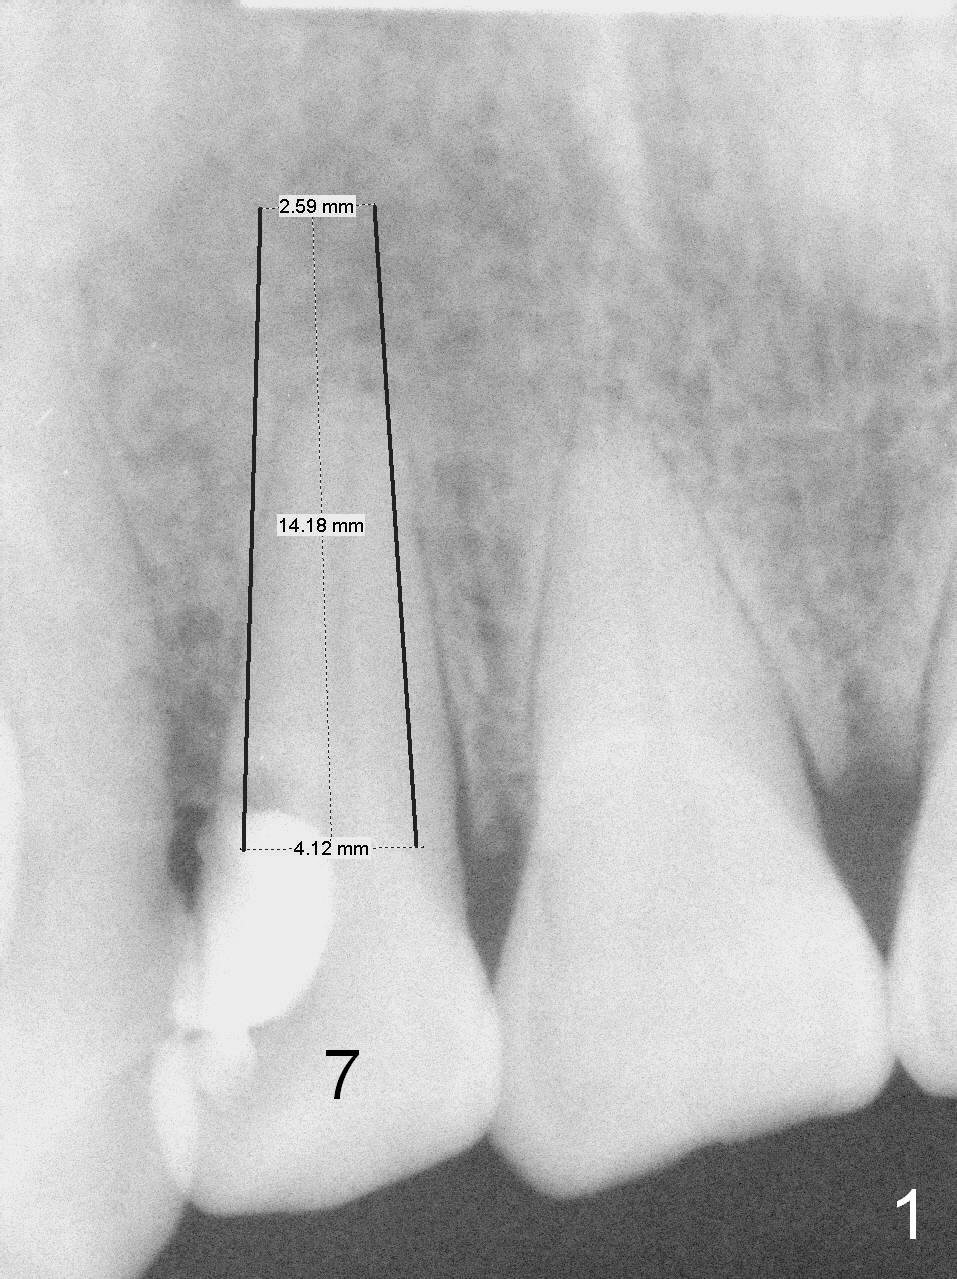

A 52-year-old man had a non-restorable lateral incisor 3 years ago (Fig.1). It fractures lately (Fig.2) with a buccal abscess (Fig.3 *) ) and fistula (>, possible severe buccal plate defect, prepare PRF). Severe deep bite (Fig.4) and malocclusion (Fig.5) will present a challenge to implant provisional restoration.

After extraction (no Antibiotic socket treatment), start osteotomy in the palatal wall for a few mm in the native bone, insert a parallel pin and check bite. Adjust the trajectory and position of the osteotomy as early as possible. If the bone is dense, extend osteotomy depth to 18 mm for a 3.8x15 or 16 implant. Otherwise 20 mm for 3.8x18 mm one. The final drill will be 2-3 mm shorter if the bone density is low.